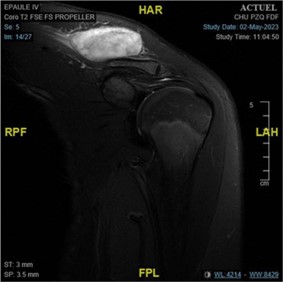

Magnetic Resonance Imaging (MIR) of the shoulder showed a well-limited oval tissue mass of 45 mm diameter within the insertion of the trapezius muscle on the clavicle, taking contrast after gadolinium injection with no signal abnormalities in muscle and bone tissue (Figure 3).

Figure 3: MIR findings.

Imaging features can help characterise the lesion and the surrounding anatomy but are also unspecific and, most of the times, insufficient to make the correct diagnosis or differentiate it from malignant lesions. MRI of Nodular Fasciitis shows various signal intensities, probably because of the combination of variability in cellularity. In general, the signal intensity of the lesion with myxoid or cellular histology is higher than that of muscle on T2-weighted images, whereas lesions with fibrous histology present as a markedly hypointense signal compared with the surrounding muscles on all pulse sequences. The coexistence of abundant collagen and a cellularity in the fibrous lesions leads to a reduction in signal intensity on T2-weighted images [2].

MIR features in our case contrast-enhanced using gadolinium revealed increased heterogeneous enhancement which are similar to MIR description in nodular fasciitis reported in the literature [2,4,10].